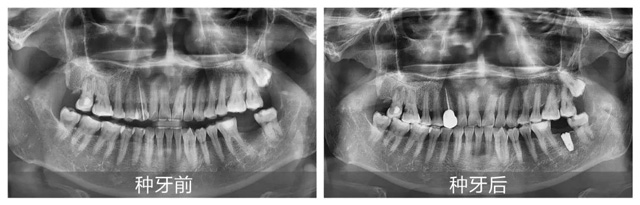

上午10:37分,手术室也已准备就绪。伴随着王志建医生深入浅出的讲解,来宾们观看了吴建方医生从术前局部麻醉、逐级备洞,再到精准植入植体以及最后严密缝合的手术全程,并纷纷就自己对种牙各环节的疑问与王志建医生进行了详细交流。

上午10:43分,吴建方医生向镜头挥手,示意手术完成。在场观众对其7分钟完成“缺牙重生”的精湛技术报以热烈的掌声和高度赞扬。